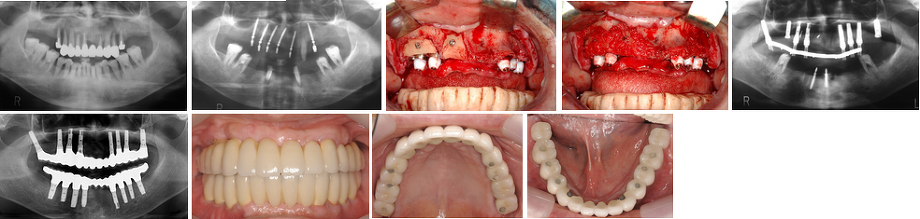

5.極度の骨欠損がある7歯欠損症例

(症例 6、歯槽骨延長術と自家骨移植)

極度の骨欠損があったが、歯槽骨延長術と下顎枝部からの自家骨移植にて審美的インプラント治療を行いました。

歯槽骨延長術では他の部位からの骨採取(骨移植の場合は必ず他の部位から骨採取が必要です)をする必要がなく、その部位の骨に切れ目を入れ、骨延長器を使って1日0.2-0.5mmずつ骨を伸ばしていく方法です。必要な量だけ骨を伸ばすことが可能であり、同時に歯茎も伸ばせる利点もあります。

非常に特殊な術式なので、行える医療機関はほとんどないのが現状です。当院では、40症例の経験があり、インプラント関係で最も権威のある 学会雑誌に掲載されました(Antero-inferior Distraction of the Atrophic Subtotal Maxillary Alveolus for Implant Placement: A Case Report.International Journal of Oral and Maxillofacial Implants (JOMI).2002; 17(3): 416-423. )

歯槽骨延長術では他の部位からの骨採取(骨移植の場合は必ず他の部位から骨採取が必要です)をする必要がなく、その部位の骨に切れ目を入れ、骨延長器を使って1日0.2-0.5mmずつ骨を伸ばしていく方法です。必要な量だけ骨を伸ばすことが可能であり、同時に歯茎も伸ばせる利点もあります。

非常に特殊な術式なので、行える医療機関はほとんどないのが現状です。当院では、40症例の経験があり、インプラント関係で最も権威のある 学会雑誌に掲載されました(Antero-inferior Distraction of the Atrophic Subtotal Maxillary Alveolus for Implant Placement: A Case Report.International Journal of Oral and Maxillofacial Implants (JOMI).2002; 17(3): 416-423. )